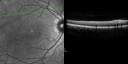

OD: Vertical C/D ratio is 0.2. There is no posterior vitreous separation and 2+ multiple macular drusen. There is no bull’s-eye maculopathy.

OS: Vertical C/D ratio is 0.2. There is no posterior vitreous separation, again there are 2+ multifocal small cuticular macular drusen.

OCT SCAN: The OCT scans were normal. Photos confirm clinical findings.

FLUORESCEIN ANGIOGRAPHY: Fluorescein angiography shows early hyperfluorescence of tiny macular drusen scattered throughout the macula in both eyes.